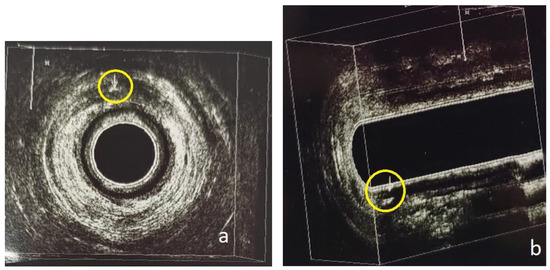

Trainees and attending radiologists were involved in the MR imaging. The MR images were finally evaluated by one radiologist with 20 years of experience who was blinded to whether the patient would also be subjected to a 3D-EAUS or not. The anal sphincter muscles, levator plate, and ischiorectal fossa were evaluated with a T1 sequence before and after gadolinium infusion. The lumen of the perianal fistulas and any secondary extensions or inflammatory liquid collections were visualized as hyper-intense tracts or cavities on T2- and STIR-weighted images. On gadolinium-enhanced fat-suppressed T1-weighted images, the fistulous tract’s wall and active granulation tissue demonstrated intense enhancement, while any fluid in the lumen was hypointense. Fibrotic scar tissue demonstrated low signal intensity on both T1- and T2-weighted images. We recorded the four characteristics mentioned in the 2.6. Methods subchapter for all visualized perianal fistulas (Figure 1 and Figure 2).

Figure 2. Patient no. 2; preoperative pelvic MRI. (a) Axial T2-weighted sequence. Intersphincteric perianal fistula, located at the 11 o’clock in the anal canal (left yellow arrow). Submucosal perianal fistula, located at the 6 o’clock in the anal canal (right yellow arrow). (b) Axial T2 fat-saturated sequence. The same two perianal fistulas (yellow arrows). (c) Axial T2 fat-sat sequence. Submucosal perianal fistula at the posterior wall (6 o’clock) of the anal canal (yellow arrow). (d) Axial T2 fat-sat sequence. Concomitant small abscess at 11 o’clock (yellow arrow).